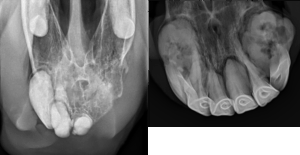

- Radiographs (X-rays): Radiographic imaging of the incisors and canines is essential for evaluating the extent of dental disease, visualizing resorptive lesions, assessing the integrity of tooth roots, and identifying secondary complications such as periapical infection or bone loss. Dental radiographs help guide treatment planning and monitor disease progression over time. (Figure 1.)

Figure 1. Radiographs (x-rays) from two different horses with significant EOTRH. Tooth roots are enlarged and rounded, with bone loss/resorption of the most severely affected teeth. - Histopathology: In cases where the diagnosis is uncertain or additional information is needed, histopathology (microscopic examination of tissues) of affected teeth can be performed after tooth extraction to confirm the diagnosis.